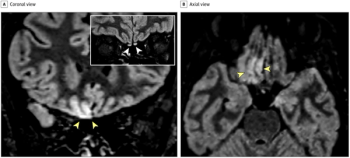

CT and MRI scans show neurological impacts.

Multiple brain regions and cerebral spinal fluid can be affected.